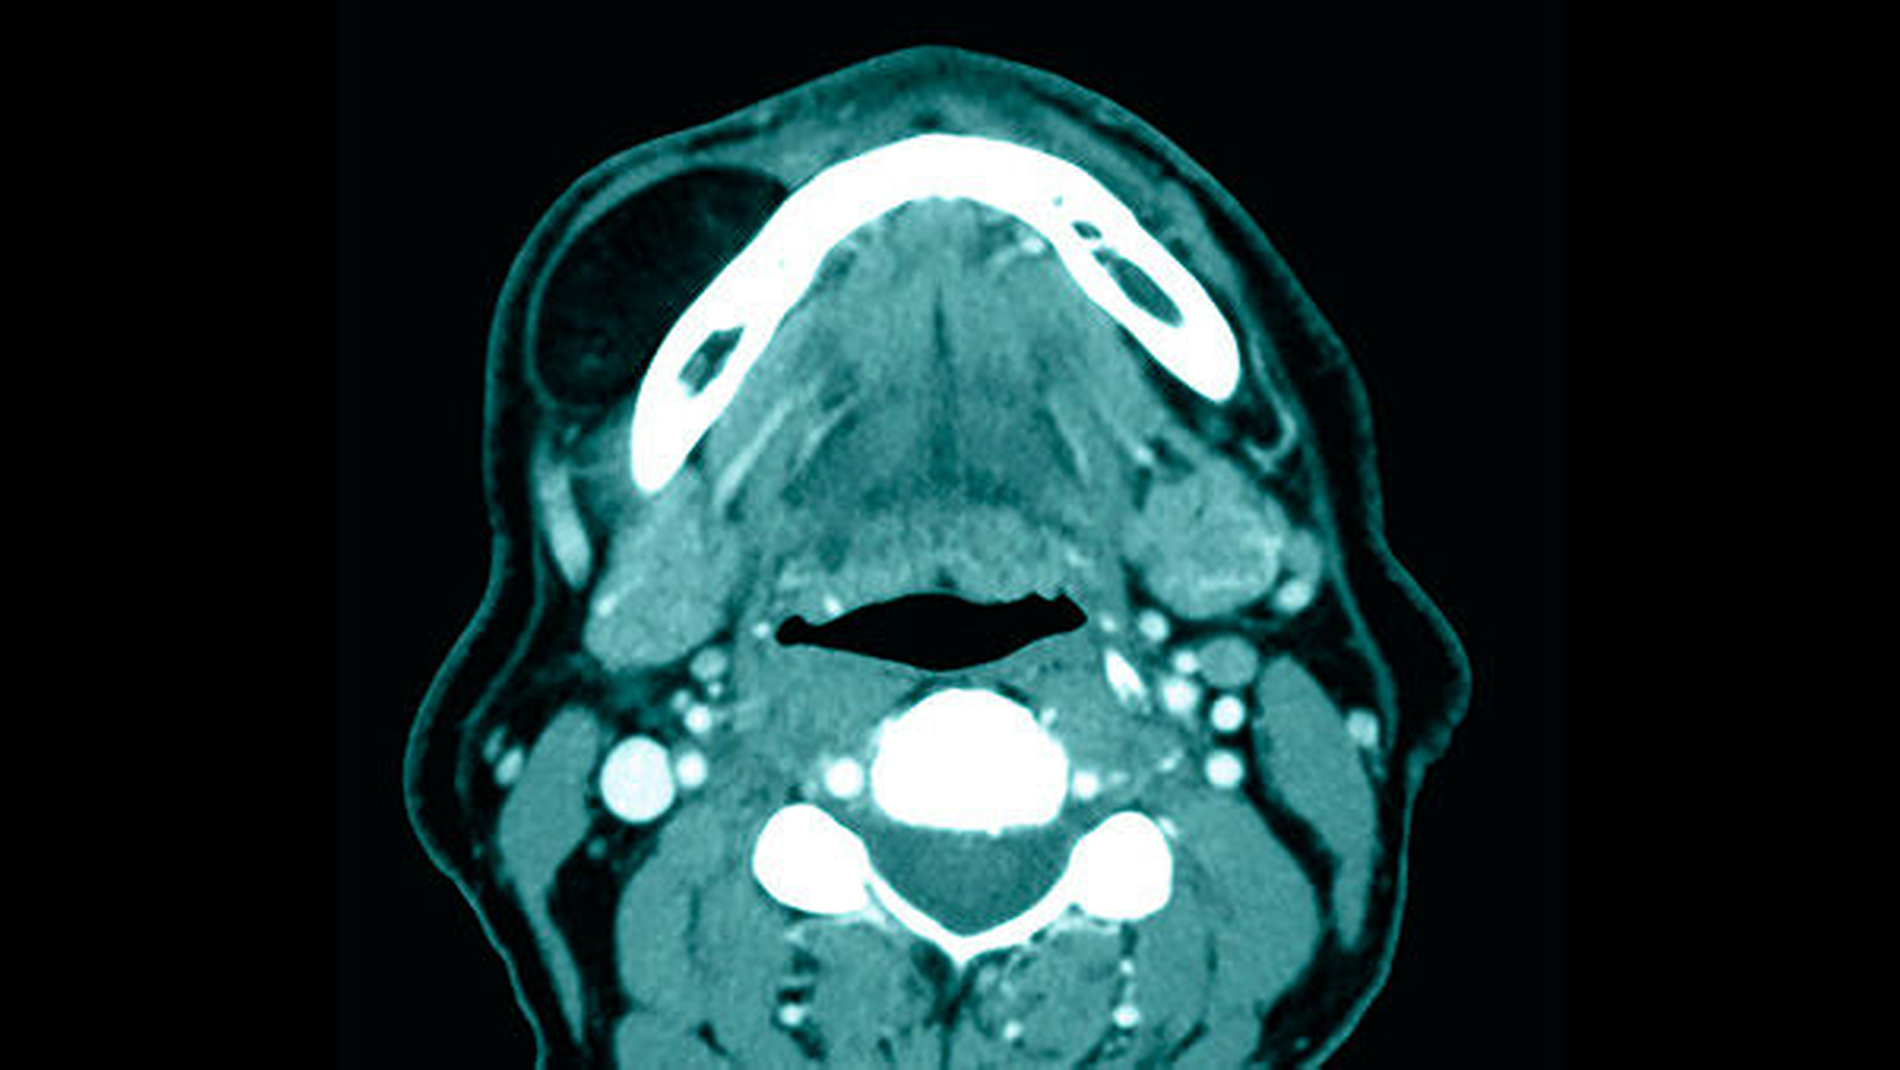

Die initiierte Computertomografie mit Kontrastmittel ergab das Vorliegen einer scharf begrenzten Raumforderung im Bereich der paramandibulären Loge rechts mit einer Ausdehnung von 3,5 cm x 1,5 cm x 4 cm. Nach ausführlicher Aufklärung des Patienten über die vorliegenden Befunde sowie über die möglichen therapeutischen Alternativen erfolgte die gemeinsame Entscheidung zur Entfernung der Raumforderung im Rahmen eines tagesstationären Eingriffs in Intubationsnarkose. Der Eingriff wurde vom Patienten komplikationslos toleriert. Die histologische Aufarbeitung des eingesandten Gewebes bestätigte das Vorliegen eines Lipoms. Hinweise für Malignität ergaben sich nicht. Im Rahmen der letzten ambulanten Nachsorgeuntersuchung des Patienten (drei Jahre postoperativ) zeigten sich reizlose Narbenverhältnisse im Bereich des Unterkiefervestibulums rechts.